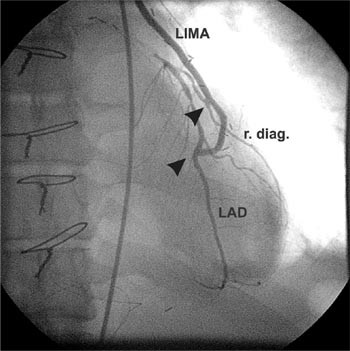

T-graft revaskularisering med a. radialis eller a. mammaria . De fleste pasienter som aksepteres til koronarkirurgi har trekarssykdom med behov for tre eller flere bypass. Sammenliknet med venemateriale er lengden av hvert enkelt arteriegraft begrenset. Selv om flere arterier er tilgjengelige, er høstingen tidkrevende. En måte å kompensere for manglende lengde er å bruke T-graft eller Y-graft. A. radialis eller høyre a. mammaria kobles da ende-til-side til venstre a. mammaria (fig 1). Metoden ble først beskrevet i 1994 av Tector og medarbeidere (27). Det er vist at man ved å bruke slike graft kan oppnå komplett arteriell revaskularisering. Bruk av T-graft reduserer instrumentering av aorta ascendens fordi proksimale anastomose sys direkte til a. mammaria. Metoden bidrar derfor muligens til å redusere forekomsten av nevrologiske komplikasjoner hos pasienter med aterosklerose i aorta ascendens. Det foreligger foreløpig mangelfull dokumentasjon på langtidsresultater av denne metoden (27, 28).

Hos 18 pasienter ble a. radialis eller høyre a. mammaria koblet ende-til-side til venstre a. mammaria som T-graft, slik at hele hjertet kan revakulariseres med et graftsystem (fig 1). I 23 tilfeller ble en arterie brukt til flere koblinger med koronararteriene (sekvensanastomose) (fig 2). Hos seks pasienter ble det i tillegg til arterielle graft supplert med venegraft til mindre koronarkar.